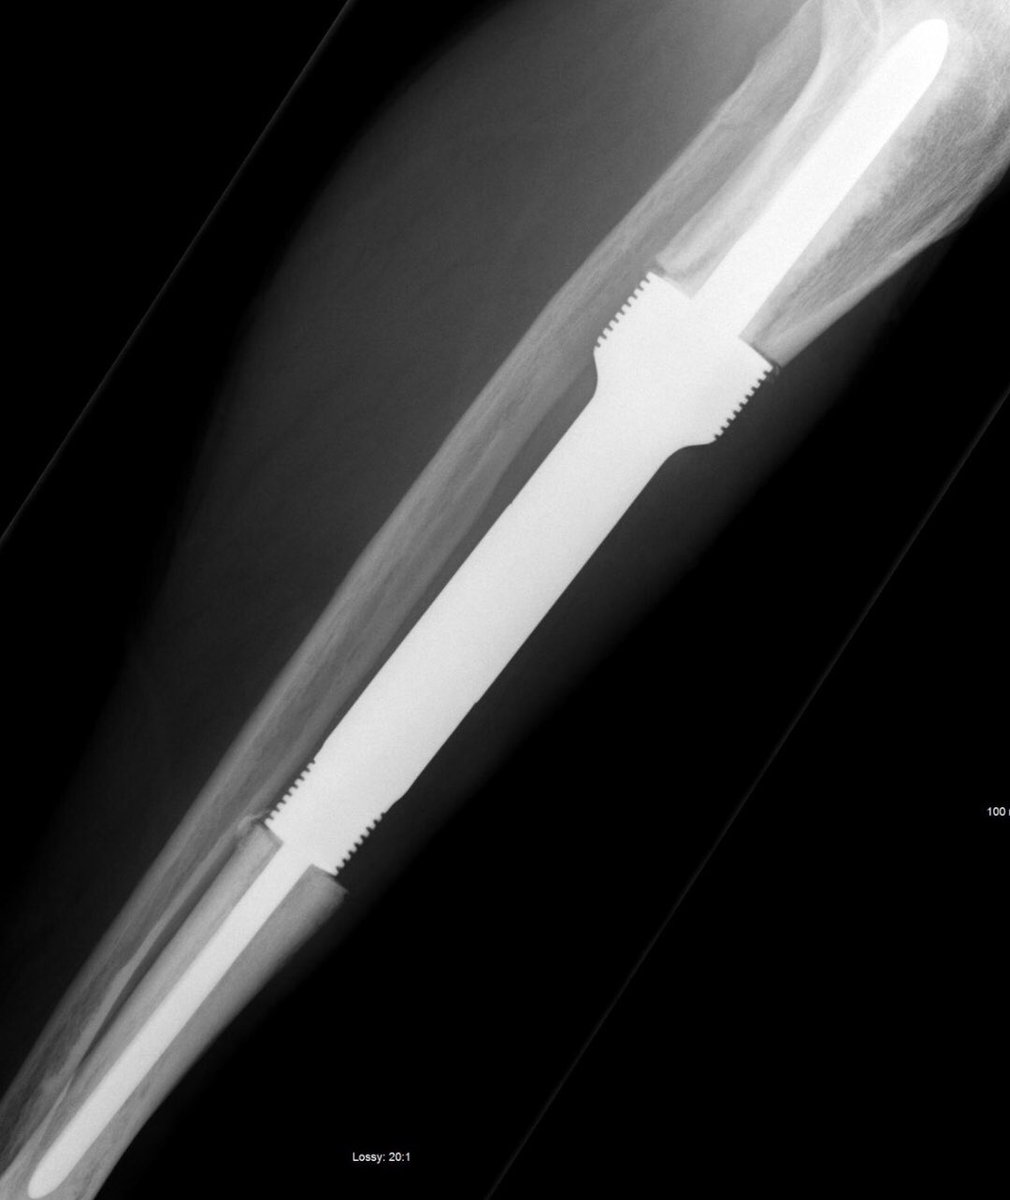

X ray of the tibia

AD presents as tibial swelling/deformity, with or without pain. The history is usually long. There is frequently a history of trauma (60% of subjects in one large series had had a previous significant traumatic episode).

A single destructive lesion or multifocal tumour,may be identified, affecting cortex and often extending to the medulla,most commonly in the mid-tibial shaft.The lesion is typically eccentric and may cause mild bone expansion,endosteal scalloping and eventually destroy the cortex